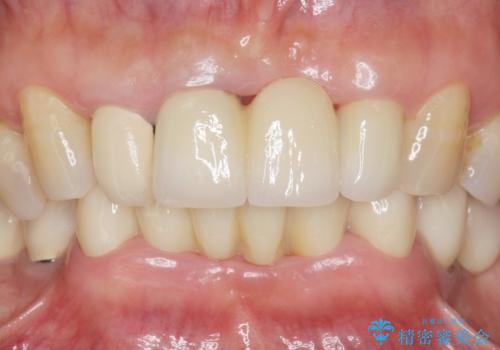

自然な仕上がりと使い心地に喜んで頂けました。

奥歯の治療もやりたいとおっしゃって下さり、今後進めていく予定です。

ジルコニアクラウン スタンダード